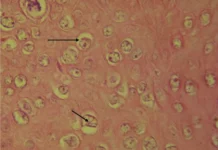

He was injured in an April 23 accident at his job at a stone mason’s workshop when a machine used to cut stone tore off most of his face and crushed his upper jaw. He received intensive treatment at a hospital that saved his life and eyesight. But an attempt to reattach his own face failed, leaving an area close to the brain exposed to infections. The damage was too extensive for doctors to temporarily seal the exposed areas. He underwent a total face transplant in a 27-hour operation.

The surgery reconstructed the area around the eyes, nose, jaw and palate and other facial areas, with the transplant running from above his right eye, under his left eye and around his face to his neck.